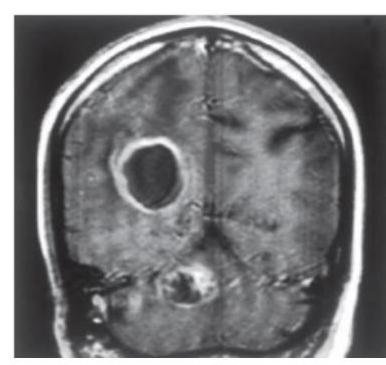

# ASPERGILOSIS ## DEFINICIÓN La Aspergilosis Invasora es la enfermedad causada por diferentes especies del **HONGO** género *Aspergillus*, a partir de un sitio de inoculación e **infección primaria**. El proceso de enfermedad incluye **angioinvasión**, **trombosis** y **tromboembolismo**; esto último, favorece la **diseminación** a otros órganos. La enfermedad invasora por *Aspergillus* afecta principalmente a pacientes **inmunocomprometidos** tales como: con **leucemia**, **linfoma**, **neutropenia prolongada**, **trasplantados** especialmente de **MO** y **pulmón**, aquellos tratados con **inmunomoduladores**, **inmunodeficiencias primarias**, con **enfermedad injerto contra huésped**, **anemia aplásica** y con terapia crónica con **corticosteroides sistémicos**. La forma invasora **incluye** las **infecciones** de las vías **respiratorias inferiores**, **senos paranasales** y **piel** como sitio de entrada. La **diseminación hematógena** o por contigüidad puede condicionar infección a nivel del **sistema nervioso central (SNC)**, cardiovascular y a otros órganos y sistemas. ## EPIDEMIOLOGÍA ## Aspergilosis Invasora: Típica aparición en **Leucemia Mieloide Aguda** y **Trasplantados**. - **Inmunocompromiso** - Mediana de edad 9-11 años (coincide con el pico de **incidencia de leucemias**) - **Neoplasias hematológicas** - **Neutropenia** < 100 cl/mm³ La presencia de **CAVITACIONES PULMONARES PREEXISTENTES** secundarias a infecciones por **Tuberculosis** facilita el desarrollo de Aspergilosis. ## Aspergilosis Broncopulmonar alérgica: - **Hipersensibilidad** asociada a **asma** - **Fibrosis quística** # CLÍNICA Es **inespecífica** en todas sus variables, por lo que es recomendable establecer la certeza diagnóstica con base en los **factores del hospedero** y sus **manifestaciones**. ## RIESGO INTERMEDIO Y ALTO - **Fiebre** y **dolor facial** - Las **lesiones isquémicas** y **úlceras** traducen un **diagnóstico tardío** Otras presentaciones: **Absceso cerebral**, **vasculitis**, **meningoencefalitis**. ## INFECCIÓN DISEMINADA ## ASPERGILOSIS CEREBRAL **Imágenes en anillo**. La aspergilosis **cerebral aislada** puede ocurrir en pacientes **inmunocompetentes**. **Signos neurológicos focales**, **alteraciones en el estado mental** y **cefalea**.  ## Enfermedad cutánea **Diseminación hematógena** o **infección local** (**inserción de catéteres**). **Quemaduras** y **heridas quirúrgicas**. **Eritema** de rápido crecimiento, con **centro necrótico**, frecuentemente **ulcerado**.  ## Aspergiloma * Una **esfera fúngica** coloniza **cavidad pulmonar preexistente** (**habitualmente una caverna tuberculosa residual**). * Se visualiza como **estructura redondeada** dentro de **cavidad pulmonar**, cambia de posición con los movimientos. * **Tuberculosis** 21 %, **no micobacterias** 20 %. ## Osteomielitis **Poco común**. **Extensión local** de **proceso pulmonar**, **sinusal**, **cerebral**. 1.ª en **enfermedad granulomatosa crónica** y **usuarios de drogas**.  # DIAGNÓSTICO ## GOLD STANDARD: CULTIVO / HISTOPATOLOGÍA / PCR / GALACTOMANANO ## CULTIVO Se debe identificar el nivel de la especie para la **susceptibilidad** de los **antimicóticos** disponibles **in vitro**. **Diagnóstico definitivo**. ## HISTOPATOLÓGICO Examen con **tinciones especiales**: PAS y/o Grocott Gomori. **Diagnóstico Definitivo**. ## GALACTOMANANO **Componente** de la **pared fúngica** excretado en la fase de **crecimiento del hongo**, siendo su nivel **proporcional a la carga fúngica** en el tejido. **Positivo en fusariosis**. **Diagnóstico Definitivo**. * Se mide en **suero** y en **lavado broncoalveolar**. * Puede haber **falsos positivos** con el uso de **pipetazo** y otros **betalactámicos**. ## RADIOGRAFÍA DE TÓRAX Se observan **cavitaciones** o **infiltrados**.  (c) Copyright 2021-2022 Joyas ENARM - Todos los derechos reservados - # TOMOGRAFÍA DE TÓRAX Debe realizarse de manera **inicial**, seguida de una **TAC de Alta Resolución** (**cortes finos de 1 mm**) si en la primera se identifica **anormalidad**. **SIGNO DEL HALO**: área de **opacidad en vidrio deslustrado** alrededor de un **nódulo** o **consolidación focal**. Se observa durante la **neutropenia** y es muy **característica** de la **infección invasora por hongos del pulmón**. **Presente** en el **60% de los casos** por 5-7 días posteriores a la **neutropenia grave**. ## TRATAMIENTO  ## **1.ª elección: VORICONAZOL** **Alternativas**: **Isavuconazol** **Efectos secundarios**: **alteraciones visuales**, **hepatotoxicidad** y **fotosensibilidad**. **FORMA INVASIVA**: **Anidulafungina**, **Caspofungina**, **Micafungina**.